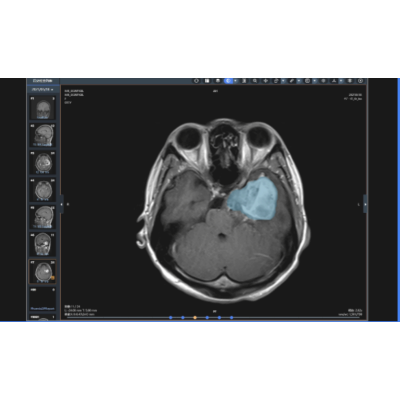

神经肿瘤辅助诊断

应用大量病例验证的神经肿瘤影像数据,能实现多种颅内肿瘤辅助定性诊断和肿瘤分级,精确输出“位置、大小、形态、边缘、信号、强化特征”等多元化信息,自动生成结构化/文本化影像报告,无缝对接影像报告编辑处理流程。提高敏感性、特异性、鉴别诊断准确性,且可为影像诊断学提供更多新征象,回馈影像医生,推动诊断模式的创新。